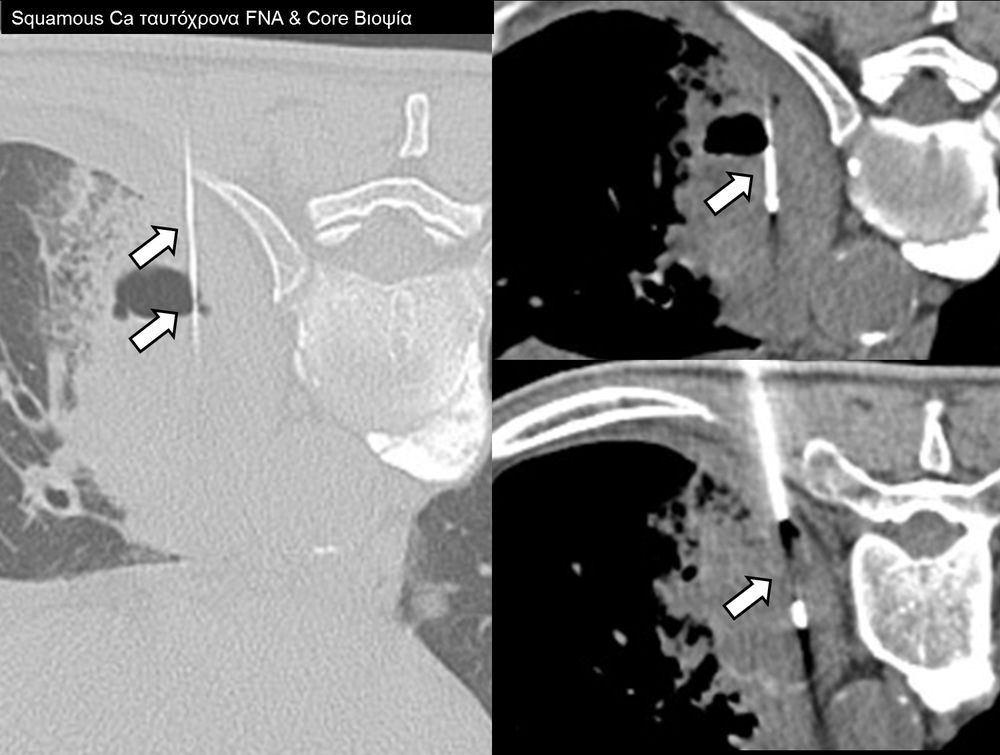

Η διαδερμική βιοψία είναι μία ελάχιστα επεμβατική μέθοδος λήψης υλικού από τον όγκο για κυτταρολογική και ιστολογική εξέταση, από εστιακές αλλοιώσεις του ήπατος, πνεύμονα, νεφρού κλπ. Συστήνεται από τον κλινικό ιατρό ανάλογα με το είδος και το μέγεθος της βλάβης και πραγματοποιείται με ασφάλεια από επεμβατικό ακτινολόγο με την καθοδήγηση αξονικού τομογράφου ή υπερήχων. Στη σύγχρονη ογκολογική θεραπεία όπου γίνεται προσπάθεια καταπολέμησης του καρκίνου σε μοριακό επίπεδο κρίνεται αναγκαία η ακριβής ιστολογική ταυτοποίηση του όγκου ώστε να εφαρμοσθεί εξατομικευμένη θεραπεία για το βέλτιστο αποτέλεσμα. Οι κατευθυνόμενες βιοψίες στοχευουν στο να παρέχουν στον κλινικό ογκολόγο το απαραίτο ιστοπαθολογικό υλικό που θα του επιτρέψει να εφαρμόσει την κατάλληλη θεραπεία για τον ογκολογικό ασθενή.